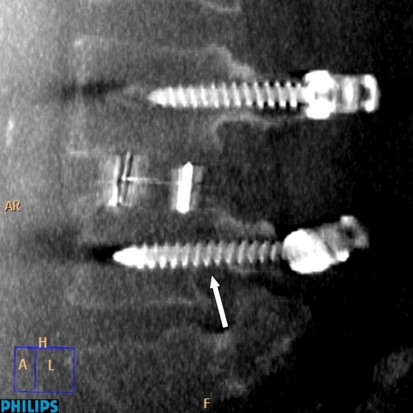

In the sagittal images (Table 2), 23 (15.1%) screws showed caudal and 10 screws (6.6%) showed cranial encroachment in Group I in comparison to 12 (6.4%) and 11 (5.9%) screws, respectively in group II (Fig. 5). The difference was proved to be statistically insignificant. Frank penetration was found in 6 (4%) screws in group I in comparison to group II which showed no frank penetration either caudal or cranial.

Fig. 5.

O-arm sagittal reconstruction image showing caudal encroachment of the left L4 screw in the O-arm group